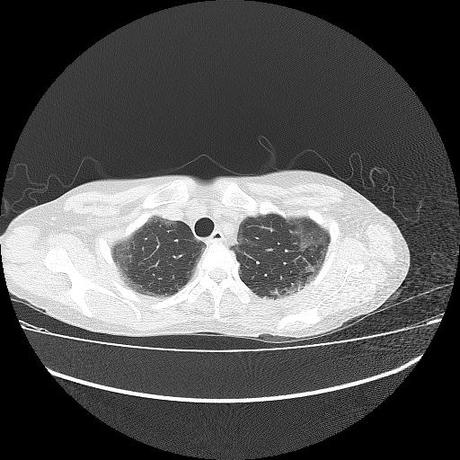

Se realiza volumen de tórax en fase simple, desde los opérculos torácicos hasta los hemidiafragmas, observándose:

El parénquima pulmonar con areas parcheadas difusas en vidrio despulido combinadas con otras areas hipodensas de baja atenuación debidas a atrapamiento aéreo y engrosamiento intersticial y zonas de fibrosis de predominio en lóbulos medios e inferiores de ambos pulmones.

- LOS HALLAZGOS PUEDEN ESTAR EN RELACIÓN A NEUMOPATIA INTERSTICIAL PROBABLE ETIOLOGIA HIPERSENSITIVA VS AUTOINMUNE/BACTERIANA/FUNGICA.